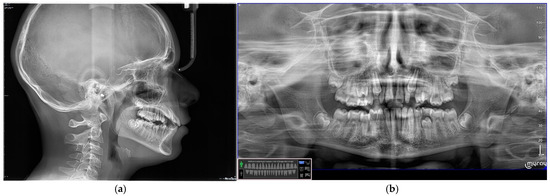

2.2.1. Patient Presentation

2.2.2. Clinical Findings

2.2.3. Diagnosis and Assessment

2.2.4. Intervention Types Considered

2.2.5. Therapeutic Intervention